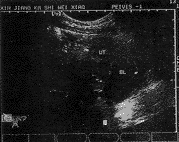

中国超声医学杂志990538 患者女,20岁。从未来过月经,自出生后就发现右腹股沟区有约2cm肿物。因右下腹痛,以腹股沟斜疝入院。超声检查盆腔、子宫未显示,提示:不除外异位子宫。入院后手术现疝内容物为子宫和附件,并将其推入盆腔。术后一周超声探查,子宫位于右下腹切口后方、膀胱右侧,其形态规整、宫腔波显示不清,附件未显示(图1)。提示:异位子宫。

图1 右下腹斜切图